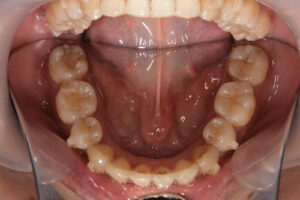

Invisalign failure - Gum recession

Invisalign failure – Gum recession

アタッチメントの下は磨けない

インビザは磨きやすい?

インビザライン治療において歯肉退縮が生じることは稀ですが、可能性はゼロではありません。

歯肉退縮は、歯茎が後退し、歯の根元が露出する状態です。これが起こる原因にはいくつか考えられます。

3. 不適切な口腔ケア: 治療中の口腔衛生管理不足も歯肉退縮の原因となることがあります。